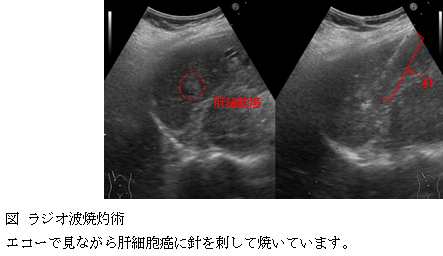

肝細胞癌の治療

当科では、ラジオ波焼灼術、肝動脈化学塞栓術、肝動注化学療法や内服治療(ソラフェニブ)を行っています。また、外科では肝切除術、放射線科では放射線治療を行っており、肝細胞癌に対する治療は網羅しています。

肝動脈化学塞栓術では、新規塞栓物質(血流を遮断する物質)である薬剤溶出性ビーズやバルーンカテーテルという特殊なカテーテル(肝細胞癌に薬を注入するため血管内に入れるチューブ)の使用などを行っており、各治療において最先端の技術を導入するように心掛けています。